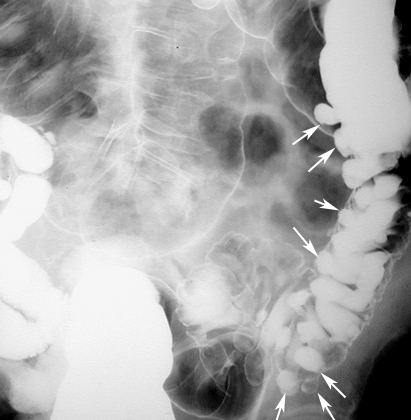

Acute Diverticulitis: A section of colon reveals acute inflammation (hyperemia, swelling) of the serosa and pericolic fat. |